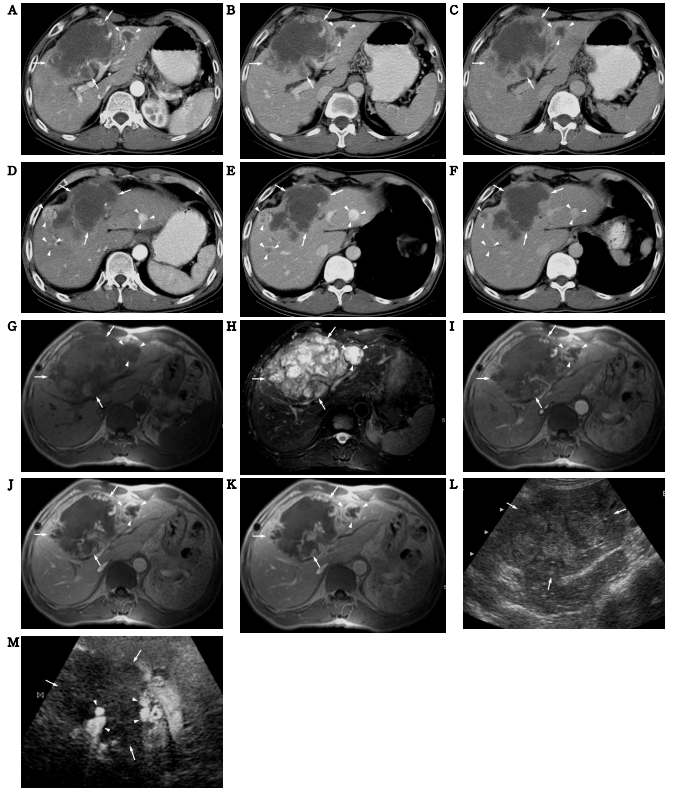

67세 남자가 상복부 동통 및 압통을 주소로 외부 병원에서 초음파검사를 받고 간종양이 발견되어 본원으로 전원되었다. 본원에 입원할 당시의 이학적 소견에서 특이 사항은 없었고, 검사 소견에서 간질환과 관련된 검사 소견을 포함해서 특이 사항은 없었다. 입원 후 전산화단층촬영(CT), 자기공명영상(MRI), 조영증강 초음파검사 등의 영상검사를 시행하였다. CT는 삼중시기 나선식 CT를 시행하였는데 동맥기(그림 1A, 1D)에 13 cm의 경계가 불분명한 주 종괴가 간의 제4 구역과 제8 구역을 점유하고 있었으며 종괴의 주변부에 불규칙한 모양의 조영증강이 관찰되었는데 주위 혈관과 같은 정도의 강한 조영증강을 보이거나 그보다 약하게 조영증강이 되어 보였다. 이 종괴는 문맥기(그림 1B, 1E) 및 평형 기(그림 1C, 1F)로 가면서 종괴 주변부의 조영증강 이 종괴 내부 방향으로 불규칙하게 진행되는 소견을 보였다. 종괴 내부로 진행되는 조영증강의 정도도 주위 혈관과 비슷하거나 약하게 관찰되었다. 간의 다른 부위에도 혈관종과 비슷한 조영증강 양상의 다양한 조영증강 양상을 보이는 네 개의 작은 종괴가 관찰되었다(그림 1A~1F).

MRI에서 주 종괴는 T1강조영상(그림 1G)에서 불균질한 저신호강도를 보였고, T2강조영상(그림 1H)에서 불균질한 고신호강도를 보였다. 특히 T2 강조영상에서 격막처럼 생기거나 둥근 모양으로 다양한 형태의 저신호강도가 고신호강도의 사이에 관찰되었다. 조영증강 T1강조영상의 동맥기(그림 1I), 문맥기(그림 1J), 평형기(그림 1K)에서 CT와 비슷한 조영증강 양상을 보였다. 간의 다른 부위의 종괴들도 T1강조영상에서 저신호강도로, T2강조 영상에서 고신호강도로 보였고 CT와 비슷한 조영 증강 양상을 보였다.

조영증강 초음파검사를 시행하였는데 조영증강 전(그림 1L)에는 내부가 불균질하지만 약간 고에코로 보이던 종괴가 조영증강 후 동맥기(그림 1M) 에 종괴의 주변부가 CT나 MRI의 동맥기와 비슷하게 강한 고에코로 조영증강되는 부분들이 있었다. 문맥기와 평형기로 가면서 고에코로 조영증강되는 부분들이 종괴 내로 차들어오는 양상을 보였다.